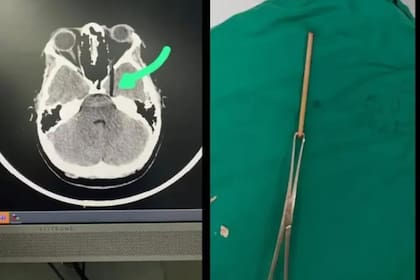

Además de estas declaraciones, también circuló una imagen correspondiente a una tomografía en donde se puede observar como se incrustó el palo en el ojo de la víctima. En redes sociales, frecuentemente aparecen recomendaciones de especialistas médicos o de pastelería que piden no realizar estas bromas, justamente por precaución de que no haya algo en el interior de la torta que actúe como soporte.